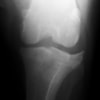

アメリカンコッカースパニエル 5歳

半年にわたる左後肢の跛行が認められるとのことで来院されました。触診にて左膝関節の疼痛、内側部の腫脹、膝蓋骨の内方脱臼を認めました。レントゲン検査にてfat pad signを伴う関節炎が認められたことから、前十字靭帯断裂と膝蓋骨内方脱臼( GradeⅢ)の併発と診断し、手術を行いました。術中の関節鏡検査にて前十字靭帯の完全断裂を確認、関節液検査にて感染を除外した後、TPLOと、滑車溝形成を始めとした膝蓋骨脱臼整復術を実施いたしました。

術前側面像

術前正面像

術後側面像

術後正面像

術前に25°であったTPAは、TPLO実施により7°に矯正されました。症例の歩行状態は良好です。